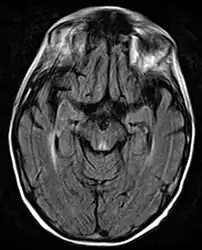

Brain atrophy associated with WKS occurs in the following regions of the brain: the mammillary bodies, the thalamus, the periaqueductal grey, the walls of the 3rd ventricle, the floor of the 4th ventricle, the cerebellum, and the frontal lobe. In addition to the damage seen in these areas there have been reports of damage to cortex, although it was noted that this may be due to the direct toxic effects of alcohol as opposed to thiamine deficiency that has been attributed as the underlying cause of Wernicke-Korsakoff Syndrome.[28]

Frequently, secondary to thiamine deficiency and subsequent cytotoxic edema in Wernicke encephalopathy, patients will have marked degeneration of the mammillary bodies. Thiamine (vitamin B1) is an essential coenzyme in carbohydrate metabolism and is also a regulator of osmotic gradient. Its deficiency may cause swelling of the intracellular space and local disruption of the blood-brain barrier. Brain tissue is very sensitive to changes in electrolytes and pressure and edema can be cytotoxic. In Wernicke this occurs specifically in the mammillary bodies, medial thalami, tectal plate, and periaqueductal areas. Sufferers may also exhibit a dislike for sunlight and so may wish to stay indoors with the lights off. The mechanism of this degeneration is unknown, but it supports the current neurological theory that the mammillary bodies play a role in various "memory circuits" within the brain. An example of a memory circuit is the Papez circuit.